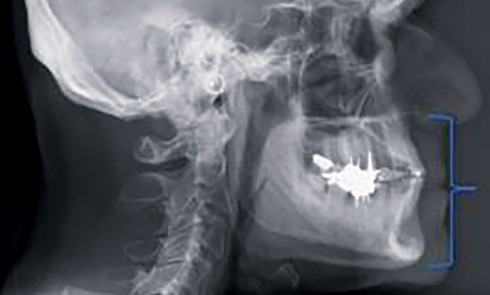

Article réservé à nos abonnés Les vrais critères de choix de la Dimension Verticale d’Occlusion thérapeutique : applications cliniques

À travers trois situations cliniques différentes, illustrées par une anamnèse, des examens cliniques et radiologiques, une réflexion est engagée pour...